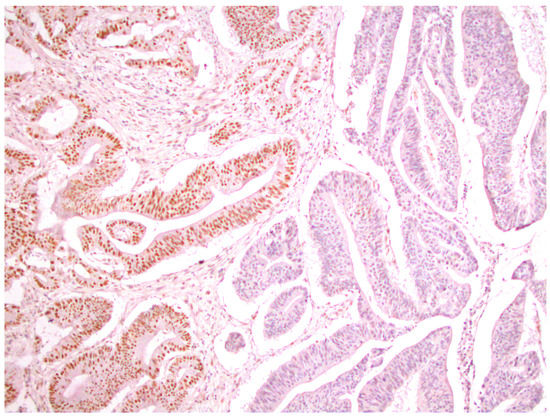

From a total of 104 patients with colorectal cancer, immunohistochemical analysis of the expression of all four MMR proteins showed that heterogeneous expression of MMR proteins (as well as deficient immunoreactivity of tumor cells (Figure 1) was present in 12 cases, while proficient expression of MMR proteins was detected in 80 tumors (Figure 2). Heterogeneous expression of PMS2 protein and heterodimeric pair MLH1/PMS2 was found in two tumors, MSH2/MSH6 was found in seven tumors (two of which also showed heterogeneity for MLH1/PMS2) and MSH6 was found only in one tumor. In seven out of twelve tumors micromorphologically, both forms of heterogeneous protein expression coexisted in the tumor tissue as intraglandular and zonal heterogeneity (Figure 3). Isolated intraglandular heterogeneous protein expression was found in two tumors (Figure 4), while zonal heterogeneity was present in three tumors (Figure 5).

Figure 4. Intraglandular distribution of heterogeneous nuclear expression of MSH2 protein in colorectal cancer, ×100.

In agreement with published results, our study found that the frequency of heterogeneous expression of MMR protein in patients with CRC was not so small and could have several different forms. Halvarsson et al. and Graham et al. described the distribution of heterogeneous MMR protein expression in patients with colorectal cancer and endometrial cancer. It was shown that in most cancers, there were areas with focal nuclear expression and/or areas with strong diffuse expression of proteins from the MMR group [24,25]. The study of Judge Joost et al. [26] provided criteria defining hMMR protein expression in tumor tissue, which was presented as intraglandular and/or zonal heterogeneity. Intraglandular heterogeneous immunoreactivity of tumor cells is defined as strong and focal nuclear expression of tumor cells within neoplastic glandular structures admixed with tumor cells showing the loss of MMR protein expression. Zonal heterogeneity of MMR proteins is presented as a diffuse loss of tumor cell immunoreactivity in multiple adjacent neoplastic glandular formations.

Initially, due to the positive nuclear expression of tumor cells, the study of hMMR protein expression was attached to the group of pMMR tumors; however, it was released as a separate group later. Our study showed 12 cases (%) of heterogeneous MMR protein expression in the entire sample. Heterogeneous expression of the PMS2 protein as well as the protein pair MLH1/PMS2 was observed in two tumors (16.7%), MSH2/MSH6 was observed in seven (58%) tumors (two of which also expressed heterogeneity for MLH1/PMS2) and heterogeneous nuclear expression of the MSH6 protein was observed only in one (8.3%) tumor. Intraglandular and zonal hMMR nuclear protein expression was registered in seven (58%) of a total of twelve cancers. Micromorphologically, intraglandular heterogeneous immunoreactivity of tumor cells was observed in two tumors (16.7%), while zonal heterogeneous expression was present in three tumors (25%). Our single-center study was also based on a comparison of demographic, clinical and pathological characteristics of CRC in relation to MMR protein expression (proficient, deficient and heterogeneous). Using the method of univariate regression analysis in our research, possible predictors of MMR protein expression (proficient, deficient and heterogeneous) were determined. These were included in the multivariate regression analysis, in which it was shown that the only independent predictors of the loss of expression were younger patients and right-sided anatomical localization of the tumor.